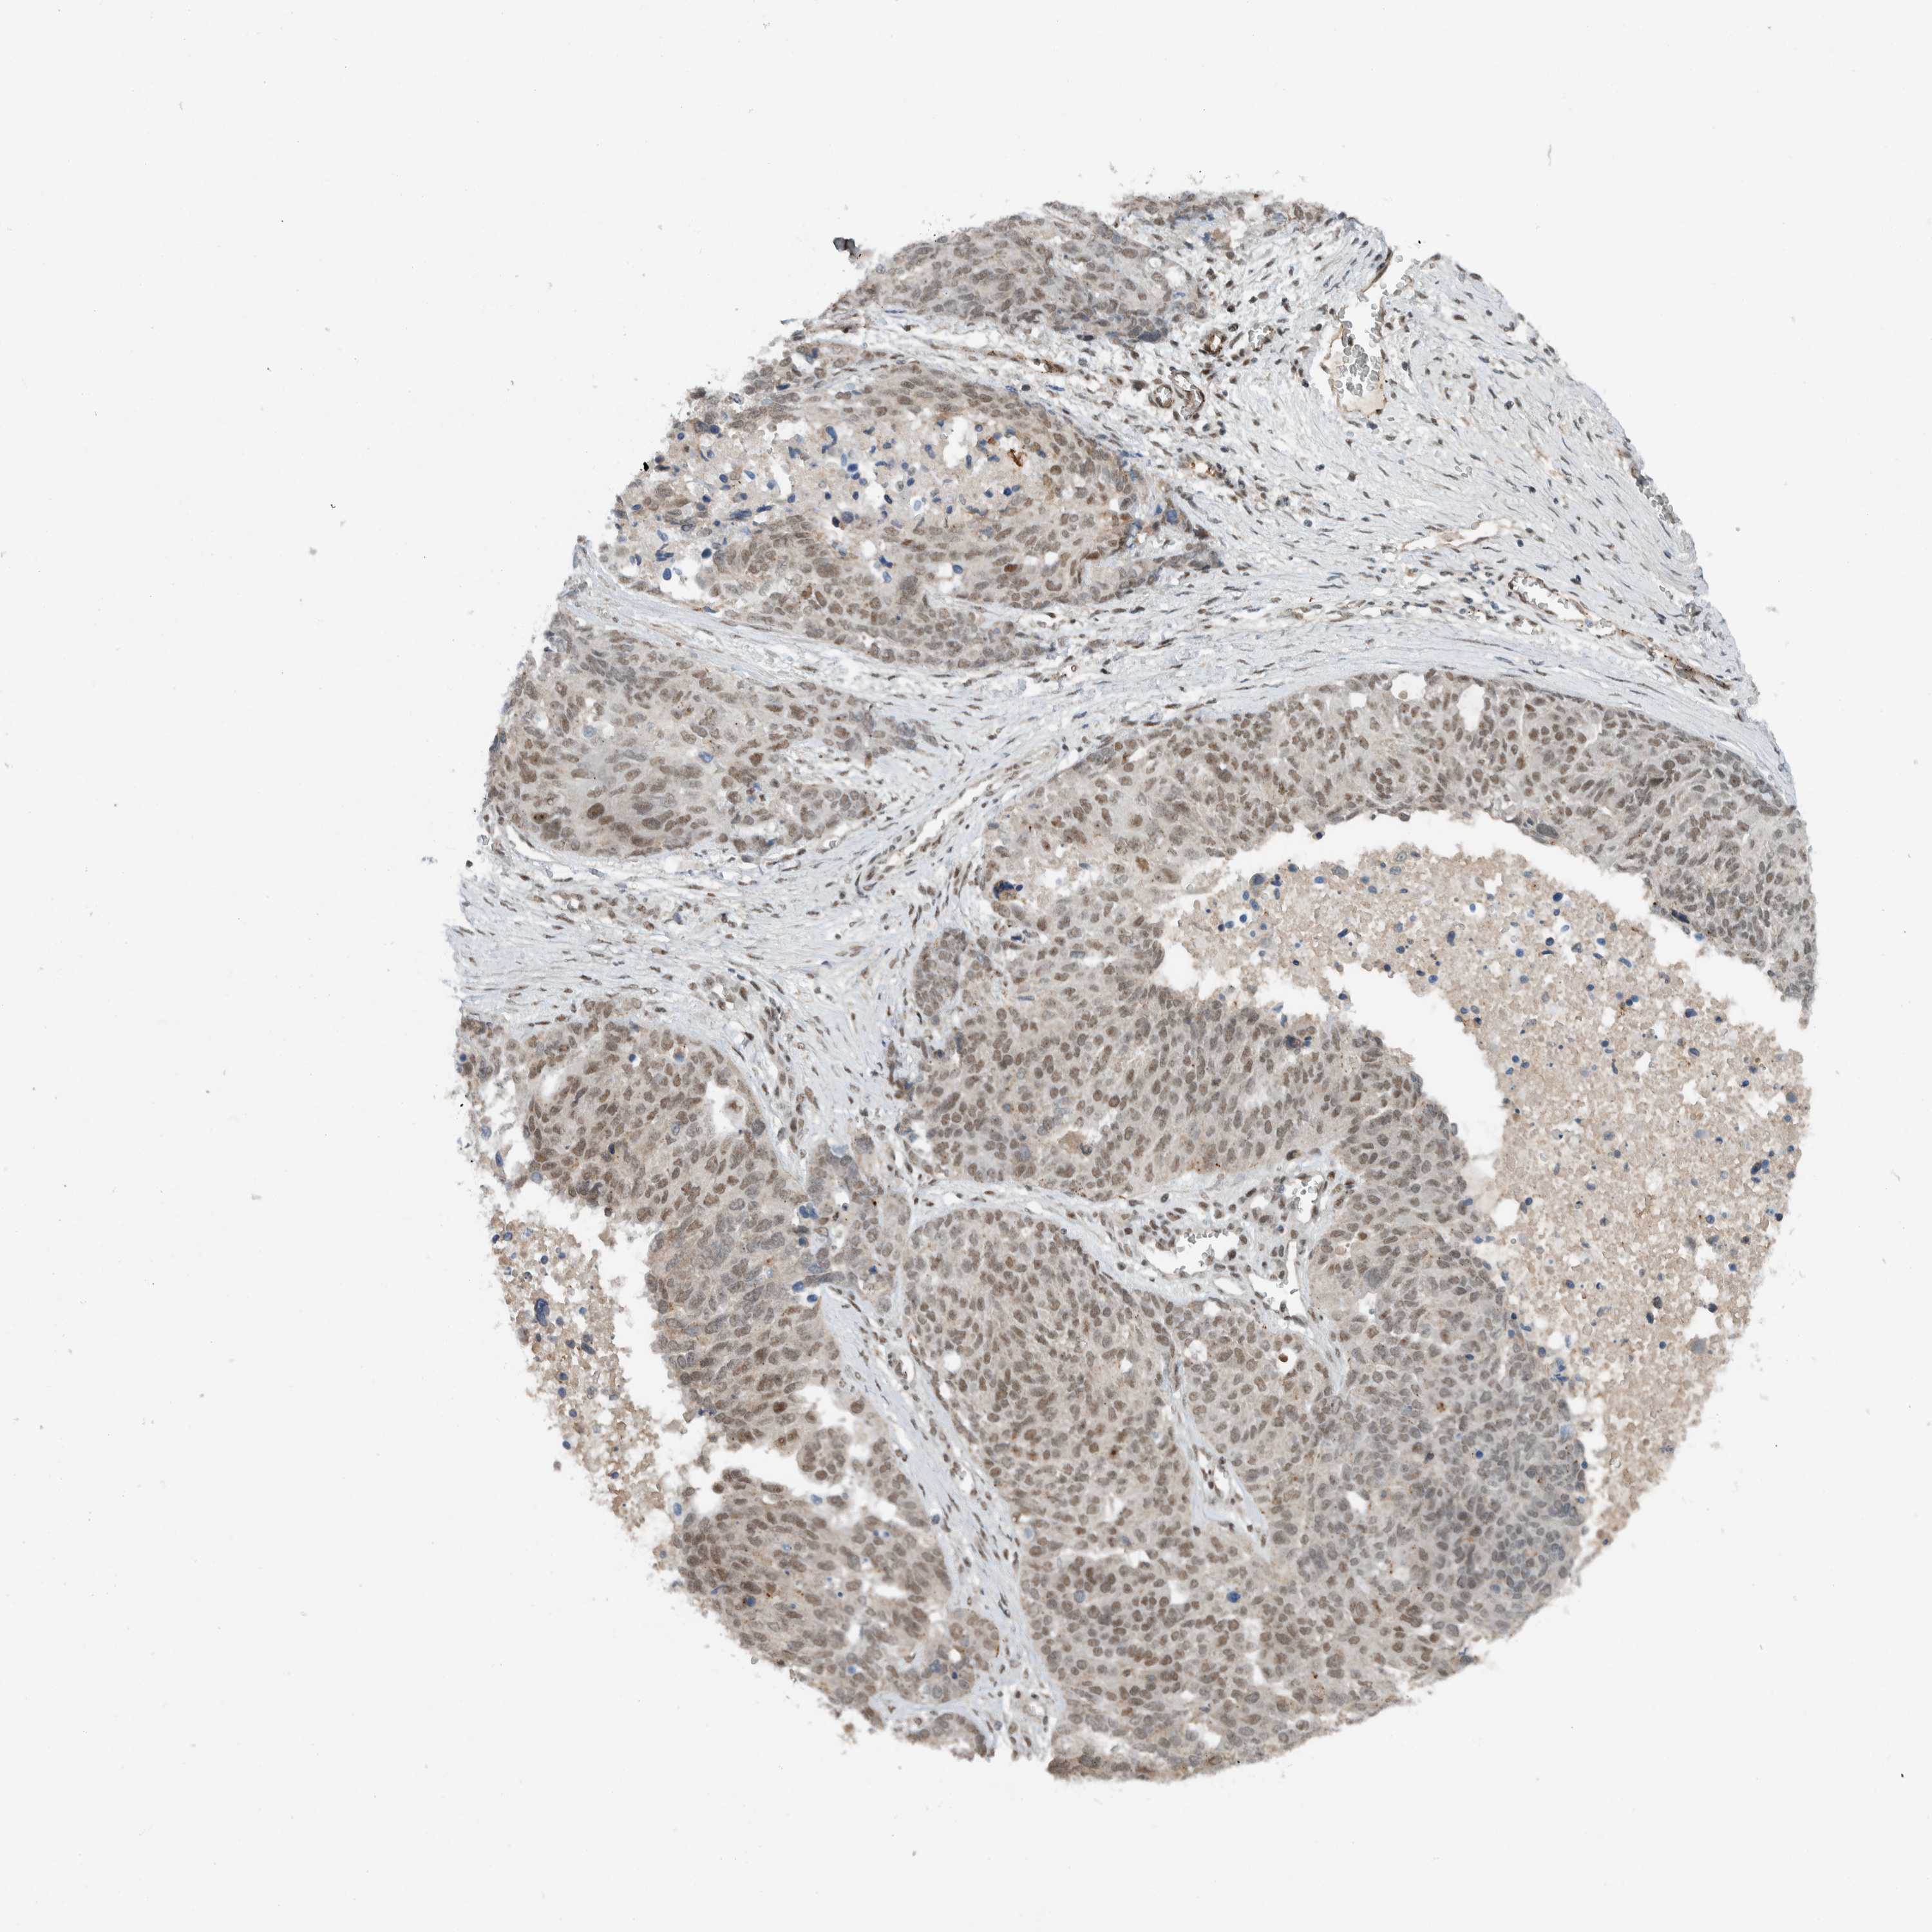

OVARIAN CANCER - Protein expressioni

A mouse-over function shows sample information and annotation data. Click on an image to view it in a full screen mode. Samples can be filtered based on level of antibody staining by selecting one or several of the following categories: high, medium, low and not detected. The assay and annotation is described here.

Note that samples used for immunohistochemistry by the Human Protein Atlas do not correspond to samples in the TCGA dataset.

Antibody stainingi

Antibody staining in the annotated cell types in the current human tissue is reported as not detected, low, medium, or high, based on conventional immunohistochemistry profiling in selected tissues. This score is based on the combination of the staining intensity and fraction of stained cells.

Each image is clickable and will lead to virtual microscopy that enables deeper exploration of all samples and also displays staining intensity scores, fraction scores and subcellular localization as well as patient and tissue information for each sample.

Antibody HPA074591

Cystadenocarcinoma, serous, NOS